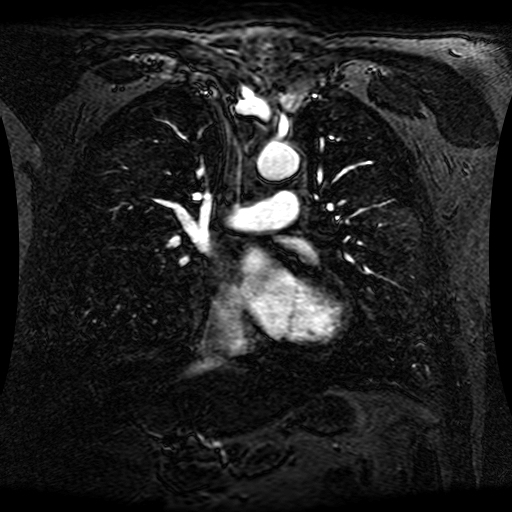

These magnetic resonance angiography (MRA) images show coronal slices acquired from consecutive anteroposterior positions within the torso. The study was performed on a 1.5T General Electric (GE) Signa imaging system with gadolinium-contrast-enhancement for visualization of the cardiopulmonary vasculature. The pulse sequence used was a 3D time-of-flight fast spoiled gradient recalled acquisition in steady state (FSPGR, TR=6.3, TE=1.4, NEX=1, FOV = 40cm, slice thickness = 1.2mm).

This sample image contains 76 frames. It is available in DICOM format (E1154S7I.dcm), as an animated GIF (E1154S7I.gif), as .ogg, .mp4, .webm, and .swf animations (one of which is shown above), or as individual PNG-format frames (see below).